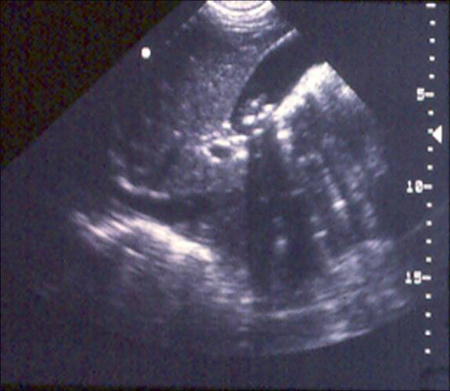

Gallbladder ultrasound demonstrating cholelithiasis with characteristic shadowing

From the collection of Dr KuoJen Tsao; used with permission